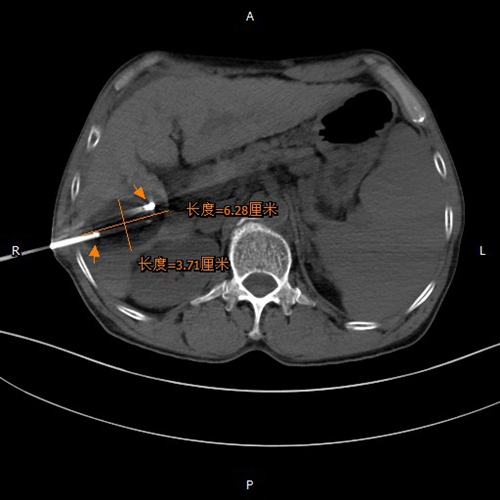

术中两根针冷冻治疗中图像

考虑到刘先生肿瘤只有“核桃”大小,根据肿瘤位置取穿刺路径合适体位,CT下定位2个穿刺点,消毒、铺巾、局部麻醉,术中冷冻温度最低至零下-150℃摄氏度,持续冷冻15分钟,循环两次,病灶损毁效果良好,手术顺利完成。